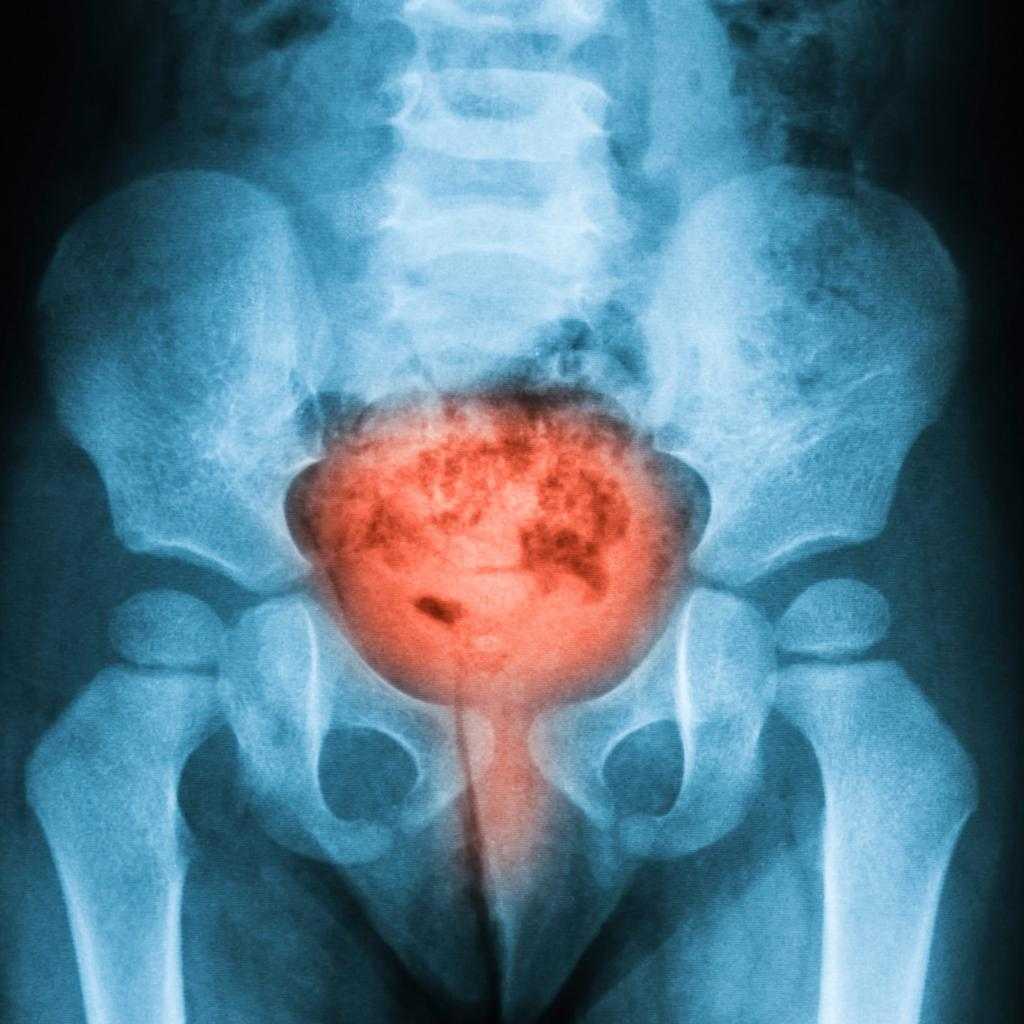

Симптомы у мужчин – не единственный повод для выставления диагноза. Чтобы определить размер и дислокацию опухоли, ее негативную динамику, проводятся лабораторные и аппаратные исследования, по результатам которых определяется стадия болезни, тактика лечения и прогноз, ожидающий пациента в будущем.

Фото, сделанные с помощью современного оборудования, малоинформативны для человека без медицинского образования. Мочевой пузырь – специфический орган в человеческом организме, с особым устройством для выполнения сложных функций.

Виды рака различают по первоначальному поражению определенного вида ткани. Самый распространенный вид – почти 95 случаев из 100 описанных – переходно-клеточный, с наибольшей вероятностью благоприятного исхода при своевременной диагностике.